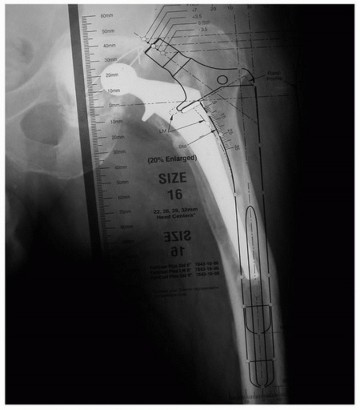

في عملية استبدال مفصل الورك، يتم إزالة رأس الفخذ التالف والجزء المتضرر من الحُق، واستبدالهما بمكونات صناعية. تتكون الدعامة الفخذية الصناعية من ساق (Stem) تُدخل في قناة عظم الفخذ، ورأس كروي يركب على هذه الساق، ليتمفصل مع كوب حُقي صناعي يثبت في الحوض. عند الحاجة للمراجعة، يتم التعامل بشكل أساسي مع استبدال هذه المكونات.

تصنيف عيوب عظم الفخذ (Paprosky Classification)

يُعد فهم جودة العظم المتبقي أمرًا بالغ الأهمية في التخطيط لجراحة مراجعة مفصل الورك. لتسهيل هذا التقييم، يستخدم الجراحون مثل الأستاذ الدكتور محمد هطيف نظام تصنيف "بابروسكي" لعيوب عظم الفخذ. يساعد هذا التصنيف في تحديد خيارات إعادة البناء الأنسب.

جدول تصنيف بابروسكي لعيوب عظم الفخذ:

| نوع العيب (Type of Defect) | وصف عظم الفخذ (Description of Femur) |

|---|---|

| I | عيوب بسيطة. مشابهة لاستبدال مفصل الورك الأولي. |

| II | تلف في المنطقة الكردوسية (Metaphyseal damage). تلف بسيط في المنطقة الديافيزية (Diaphyseal damage). |

| IIIA | فقدان العظم في المنطقة الكردوسية الديافيزية (Metadiaphyseal bone loss). يمكن الحصول على تثبيت احت |